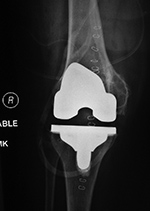

Unicompartmental knee prosthesis placed in lateral knee compartment |

50 year-old man with lateral knee compartment degenerative osteoarthritis |